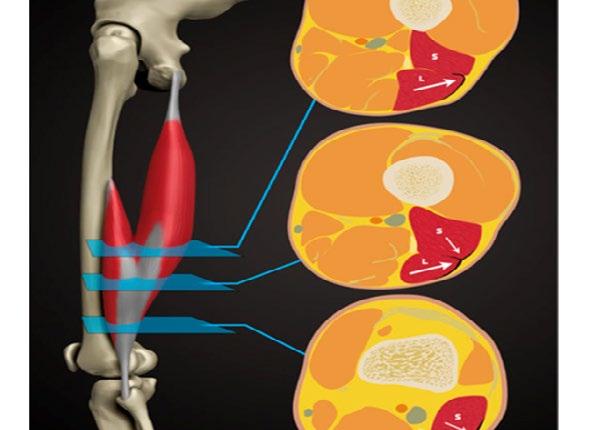

Figure 1: Reproduced from Entwisle et al. The anterolateral epimyseal surface of the long head (L) condenses to form the proximal portion of the distal musculotendinous junction. The opposing epimyseal condensations at the anterolateral aspect of the long head (L, large arrow) and the posterolateral aspect of the short head (S, small arrow) form the midportion of the distal musculotendinous junction that appears T-Shaped.

T-Junction Injuries

It is not just intramuscular tendon injuries that have particularly high re-injury rates. Consideration needs to be given also to the distal hamstring, which may have its own characteristics. Kenneally-Dabrowski, et al. 12 noted that amongst a group of professional rugby players, distal hamstring injuries were the injuries typically classified as more severe. Entwisle, et al. 13 was the first to describe what is now known as the T-Junction of the distal hamstring. This is the confluence of the epimyseal surfaces of the biceps femoris long head and short head (Figure 1). These authors report re-injury rates for this sub-type of hamstring injury at 70% for the higher grade injuries, which must be the highest reported re-injury rate for any muscle injury. 13 Similarly, Kayani, et al. 14 noted 55% recurrence rates from conservatively managed injuries to this area. Shamji, et al. 7 in their group of professional footballers at Aston Villa found that most of the re-injuries they had, were indeed in the region of the T-Junction.

All in all, the existing data, and our experience, suggest that these are a particularly challenging injury tooperhaps even more challenging than intramuscular tendon injuries. These are not rare injuries – 18% of all hamstring injuries at Leinster Rugby over a 5-year period involved the T-Junction.

a recent study Gronwald, et al. 16 described using video analysis the mechanism of 52 hamstring injuries in elite German soccer. It was noteworthy that 27 of these were stretch type, and often occurred following contact from an opponent. This matches our own findings in rugby union, where trunk flexion and ipsilateral rotation were frequently associated with hamstring injury 17

In addition, while other authors have suggested that sprint type injuries tend to cause injury to the biceps femoris, and slow stretch type injuries to cause injury to semimembranosis, 18 19 our group have repeatedly detected a theme amongst athletes with T-Junction injuries (see Figure 2, reproduced from Kerin, et al. 17). Frequently these injuries occur during late swing phase (or early stance), with a rapid ipsilateral trunk rotation (often to catch a pass, make a tackle, reach for a ball or to look behind). If this is confirmed to be a pathognomic mechanism, it could be helpful in aiding clinicians and athletes in both detecting and optimally managing these challenging injuries. If this position is the position of injury, then we may consider ipsilateral trunk rotation in trunk flexion, hip flexion and knee extension a position of ‘end stage’ rehabilitation and periodise our exercise selection accordingly.